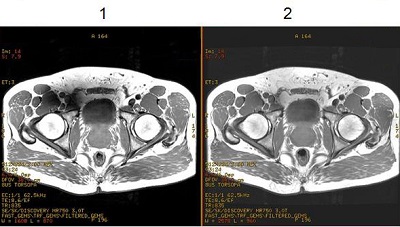

Figure 1. Images acquired with Quadrature (CP) and Preset RF Drive modes

1Image with RF Drive set to Quadrature (CP) mode.

2Image with RF Drive set to Preset mode. Note the improved homogeneity.